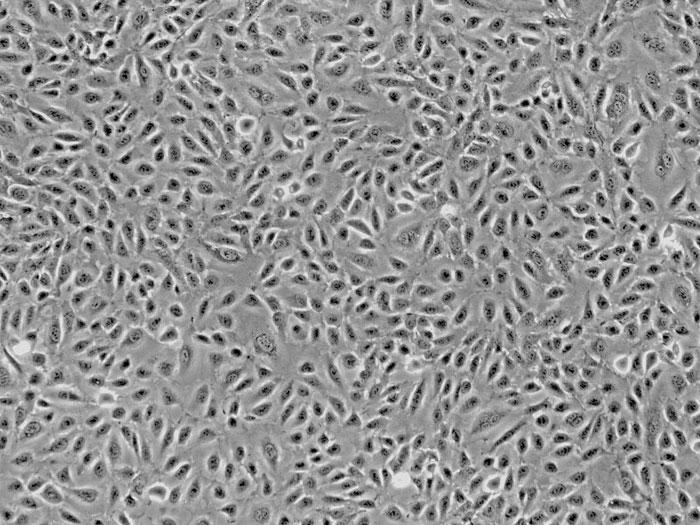

ScienCell社では、HUVEC(ヒト臍帯静脈内皮細胞)を販売しております。

HUVECは、循環器領域における医薬品開発、高分子輸送、血管形成および血管新生の研究などの実験に使用されています。